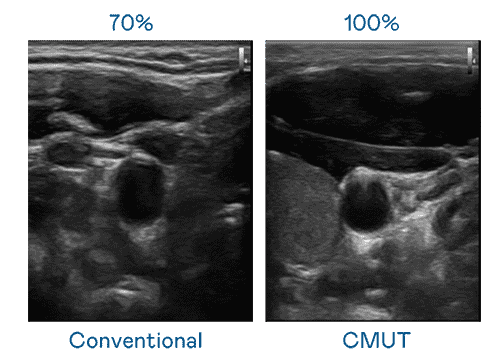

CMUT 技术是一种用电容式微机电元件来产生超音波讯号的技术。。与传统 PZT 压电式技术相比,,,,CMUT 频宽增加 30%,,,,更宽频的超音波讯号让影像解析度大幅提升,,,,是实现高影像品质医疗超音波扫描、、促进精准医疗发展的关键技术。。。

超音波影像的解析度高低,,,,首先取决于探头能发出的讯号频宽。。人生就是博 CMUT 可提供高清晰的超音波讯号,,,提供高频宽、、、高灵敏度、、影像纹理细节更高的超音波影像,,协助医护人员缩短影像判读时间及利用精准的医疗影像进行诊断。。。